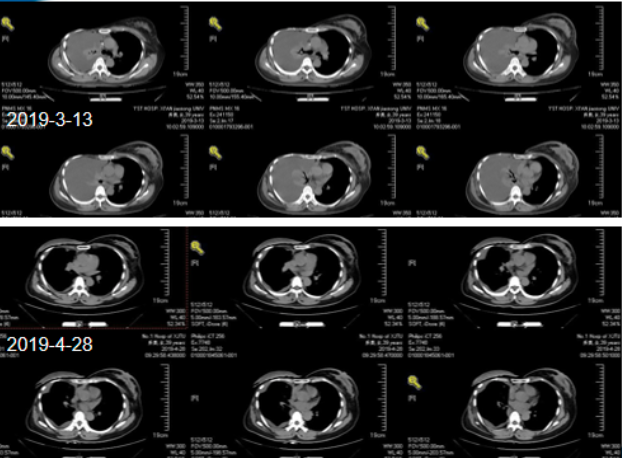

病情演变:2019-3月感气短,活动加重,夜间平卧困难,伴间断咳嗽,咳少量白痰。胸部CT(2019-3-13):1.右侧大量胸腔积液并右肺不张,右侧胸壁、背部皮下软组织肿胀;右侧第5、9肋骨多发低密度灶,骨转移瘤?

急诊行胸腔置管引流积液,并予以对症支持治疗

PET(2019-3-20):1.右乳癌术后改变,左侧乳腺腺体密实、左乳头周围皮肤增厚,葡萄糖代谢增高,考虑乳腺癌;颈部、纵隔、左侧腋窝、腹腔及腹膜后多发淋巴结转移,右侧胸膜转移,多发骨转移,多发肌肉转移;2.右侧液气胸,右肺炎症;肺下叶外基底段小结节,建议观察。